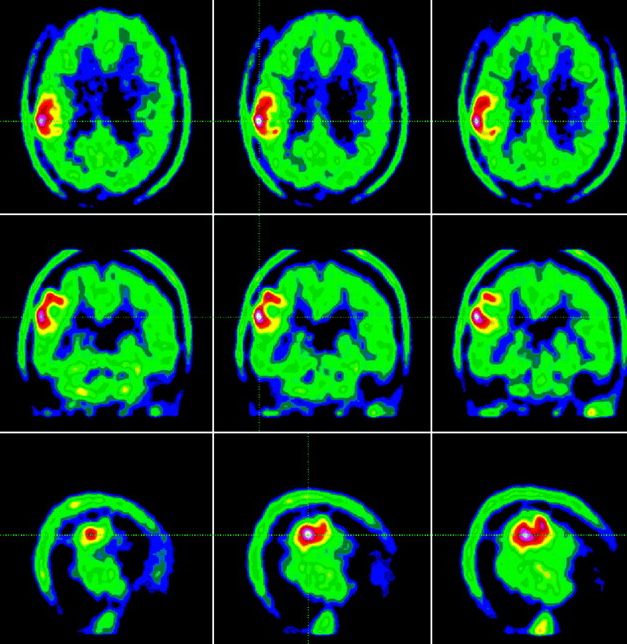

CT Compared with PET-CT

PET-CT combines metabolic imaging with anatomical detail, allowing clinicians to evaluate tumor activity, recurrence, or treatment response. While PET-CT is valuable in selected neuro-oncology cases, it is not typically used as an initial diagnostic tool.